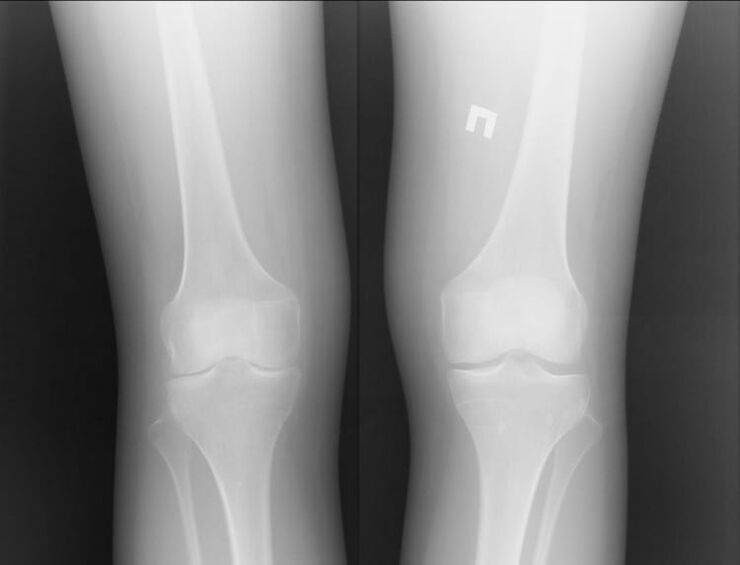

Naturally, both of these diseases are quite serious and it is difficult to say which one is worse.However, we can consider the example of a problem in the knee joint.With arthritis, that is, with inflammatory processes, the patient can be helped.

Most often this occurs due to other infections occurring in the human body.If they are cured and the inflammation of the joint is removed, then knee arthritis will no longer bother you.

Arthrosis is a completely different story.This is an independent disease caused by problems in cartilage tissue.Often this cannot be done without surgical intervention.This is followed by another long recovery process.